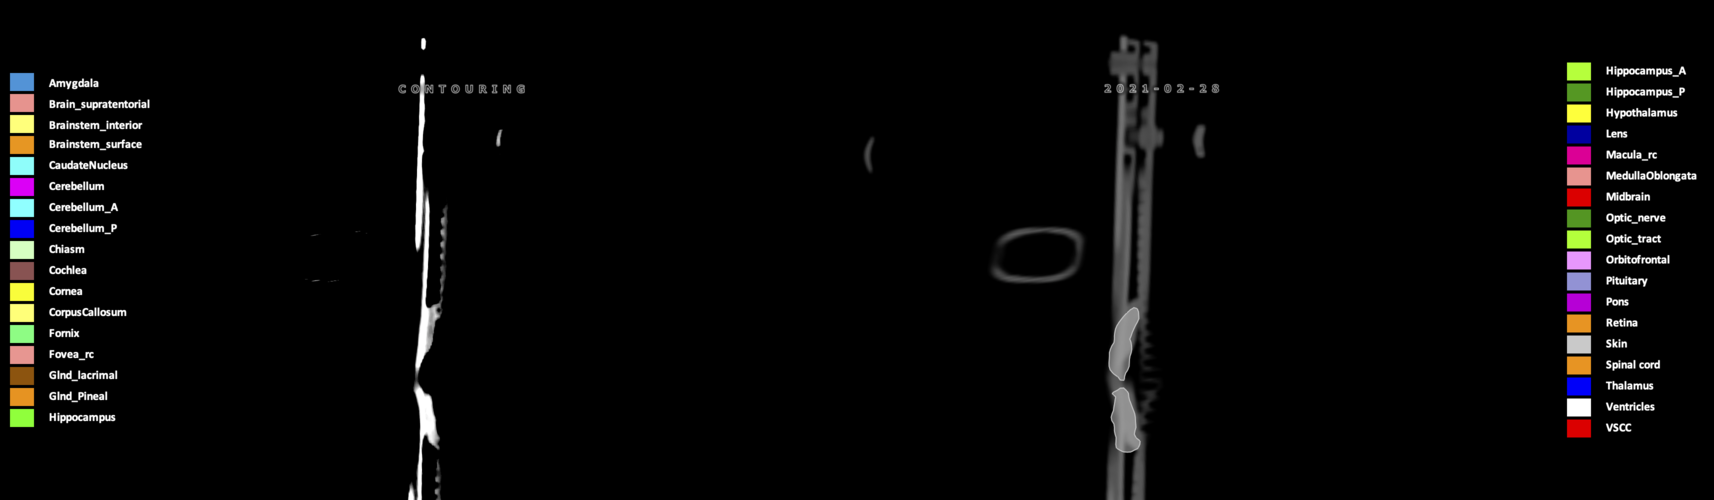

Eekers et al. have published an international neurological atlas for contouring of organs at risk in consensus with the European Particle Therapy Network (EPTN) in 2018 and an update in 2021. The purpose of this consensus atlas is to decrease inter- and intra-observer variability in delineating OARs relevant for neuro-oncology.

Included are all OARs known to be relevant for radiation-induced toxicity in neuro-oncology: brain, brainstem (midbrain, pons, medulla oblongata), chiasm, cerebellum (anterior & posterior), cochlea, cornea, hippocampus (anterior & posterior), hypothalamus, lens, lacrimal gland, optic nerve, pituitary, skin, and vestibular & semicircular canals. To further facilitate research on cognition, vision and radiological changes after irradiation of the brain, potential clinically-relevant OARs are included: amygdala, caudate nucleus, cerebellum (anterior & posterior), corpus callosum, fornix, macula, optic tract, orbitofrontal cortex, periventricular space (PVS), pineal gland, and thalamus.

We propose this atlas is used in photon and particle therapy in order to derive consistent dosimetric data. When required this atlas will be updated according to new insights.

Three-dimensional delineation of the 25 consensus OARs for neuro-oncology are shown on CT (WW/WL 120/40, 3000/600), 3T MR images, (T1Gd, T2FLAIR 1mm) and 7T MR (MP2RAGE 0.7 mm). All are presented in transversal, sagittal and coronal view.